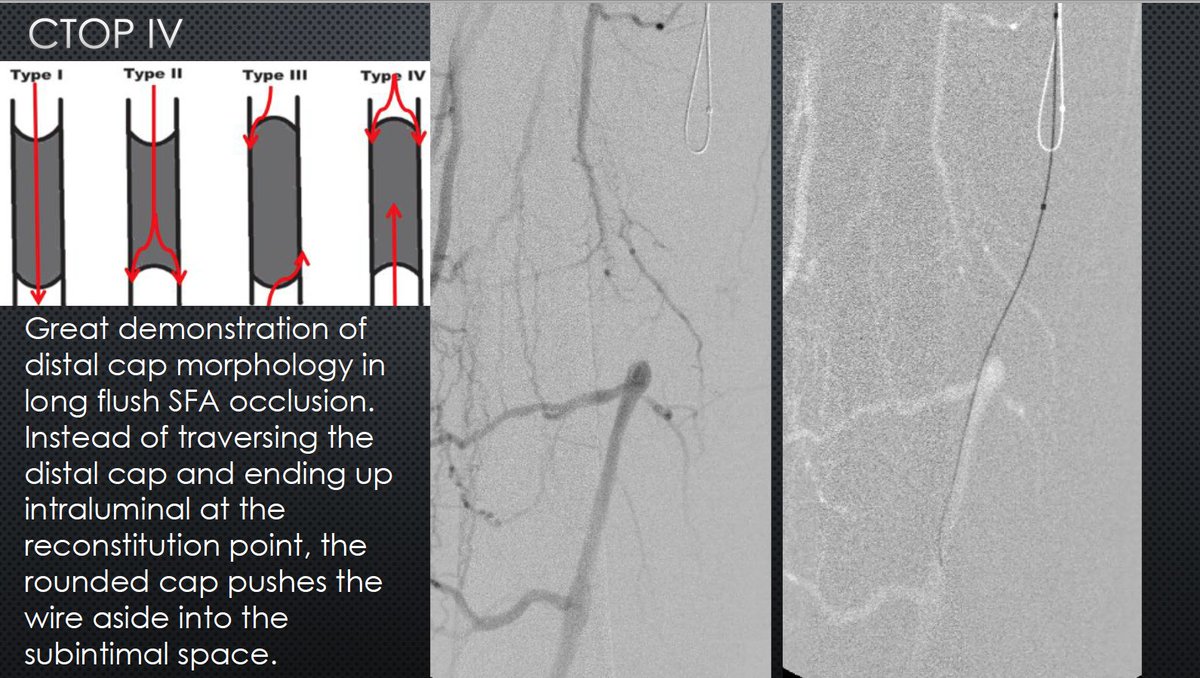

The best example of CTOP IV I've seen clinically. Know the techniques! Procedures failed by others become routine when you understand the pathology. #CLIFighters #MyLegMyLife #Can'tCTOPWon'tCTOP @SOBE_Vascular @kmadass @SDhandMD @Mustapja @FadiSaab17 @LessneVIR @SIR_ECS @SIRRFS

Watts_IR's tweet image. The best example of CTOP IV I've seen clinically. Know the techniques! Procedures failed by others become routine when you understand the pathology. #CLIFighters #MyLegMyLife #Can'tCTOPWon'tCTOP @SOBE_Vascular @kmadass @SDhandMD @Mustapja @FadiSaab17 @LessneVIR @SIR_ECS @SIRRFS